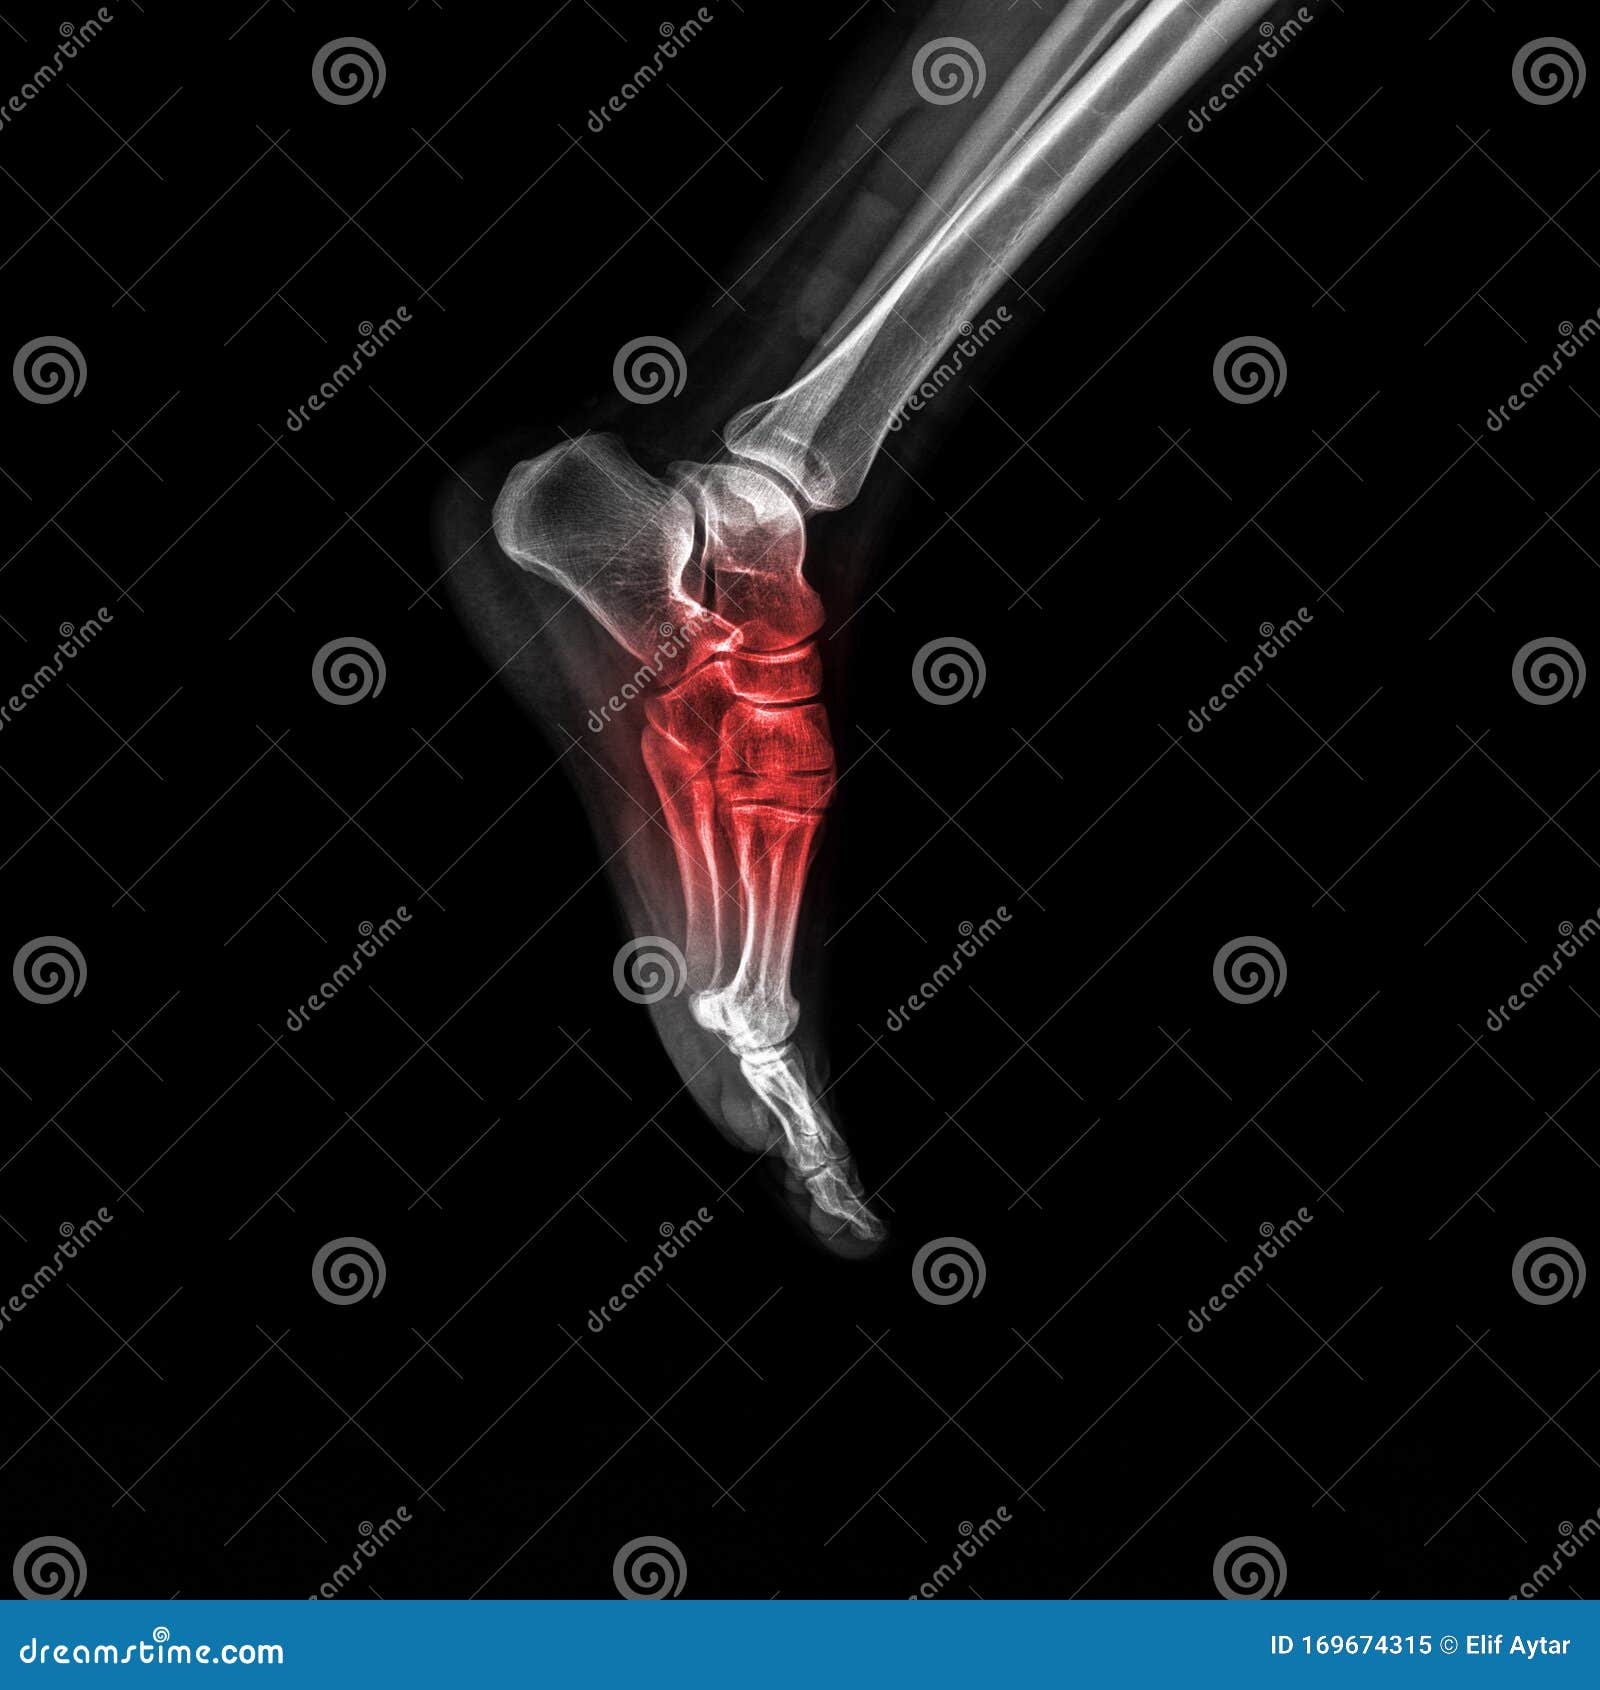

From www.dreamstime.com

Foot And Ankle Pain On Xray, Isolated On Black Background Stock Image Foot Pain Xray Bony tenderness at the navicular. Calcaneal apophysitis, also known as sever disease, is the painful inflammation of the apophysis of the calcaneus. If pain is severe enough or if there has been an injury, your doctor. [1] may not be sufficient to identify malleolar fractures. Bony tenderness at the base of the 5th metatarsal. All common forms of arthritides affect. Foot Pain Xray.